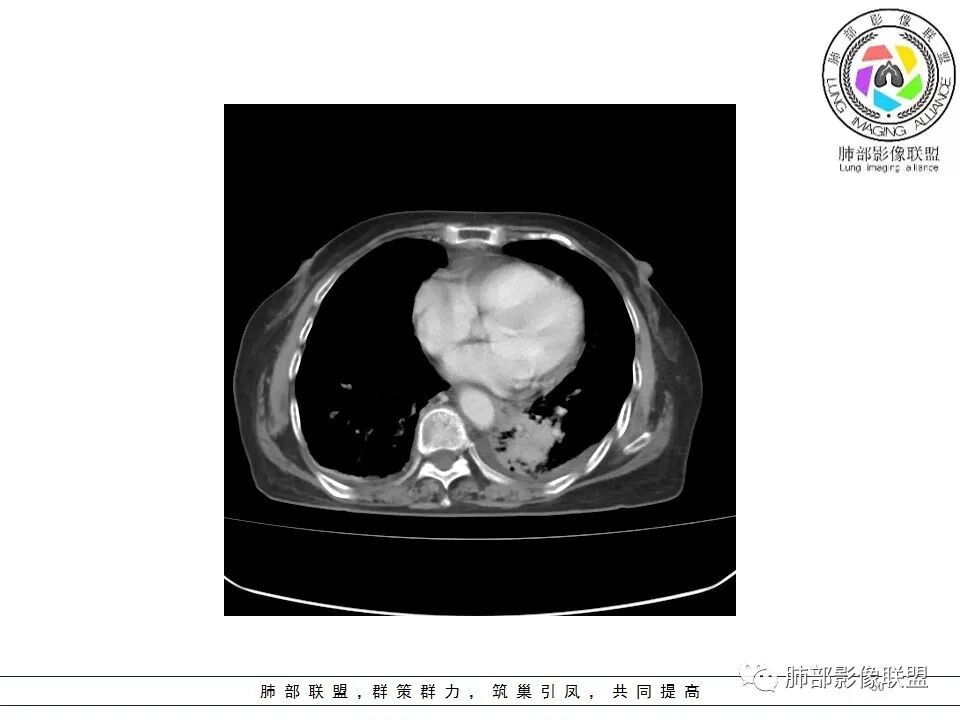

一切∮随缘: 左肺下叶脊柱旁可见大片状实变,跨多个叶段,宽基底与胸膜相贴,胸膜下可见积液,周围伴有空洞,平扫密实欠均匀,增强扫描可见低密度坏死,及血管束穿行,临床:女性,反复咳嗽咳痰7天,余未提示异常,无实验室指标,考虑:慢性脓肿(OP),放线菌?奴卡?腺癌?完善支气管镜,穿刺送培养,病理学检查。

?? 玫: 女,78岁,反复咳嗽,咳痰一周,左侧胸腔积液,贫血,左肺下叶片状实变影,边界清晰,病灶呈宽基底与胸膜相连,病灶内密度不均,增强扫描呈不均匀性强化,病灶内坏死,考虑肺脓肿可能,鉴别鳞癌,腺癌。

不吝慷慨: 左下肺肿块样病变,好像有体循环供血,肿块内血管漂浮,基本走行自然,所以综合考虑肺段隔离症,有低密度坏死区及胸腔积液,考虑合并感染。鉴别一下淋巴瘤

宇宙: 左肺下叶后基底段肿块,边缘毛糙,后基底段支气管阻塞,明显不均匀渐进强化,其内血管清晰自然,可见坏死灶,部分边界清,左侧胸水,考虑炎性病变,鉴别腺癌

金豆 (刘权威): 门诊病人,左肺下叶实变,肺不张(血管造影征),有囊变'坏死,与食管关系密切,大的方向炎症,食管支气管漏,这个年龄要警惕恶 鳞癌。

飞鹰行动: 女,78岁,反复咳嗽,咳痰七天,左肺下叶纵膈旁团片状实变影,边界清晰,局部膨胀性生长,病灶内密度不均,增强扫描病灶内呈不均匀性强化,部分坏死区边界不清晰,内可见血管造影征,部分坏死区边界清晰,可见环形强化,感染性病变是有的,需要警惕合并占位,腺癌伴感染?

小兜: 女,78岁 反复咳嗽咳痰7天,左肺下叶脊柱旁实变影,平扫密度不均,内部可见低密度灶,增强扫描明显不均匀强化,内部血管走行自然,可见多发低密度坏死区,坏死区边界清晰,少量胸水,考虑脓肿

丽: 老年女性,病程短,左肺下叶实变密度影,边缘模糊不清,增强后明显不均匀强化,内可见坏死,血管走形自然,考虑炎性病变伴脓肿形成

风儿: 老年女性,咳嗽咳痰7。左肺下叶后基底段肿块,边缘毛糙,外缘轻度膨隆,支气管有阻塞,强化不均匀,其内血管清晰自然,可见边缘清晰坏死灶,少量胸水,考虑:炎性-炎症机化伴慢性脓肿、放线菌;肿瘤:腺癌

尘缘: 老年女性,咳嗽咳痰7天,影像表现:左下肺肿块,内部多处坏死,胸腔积液,增强内部血管走行尚可,血管破坏不明显,大的坏死边缘清楚,大的坏死后面一部分不均匀强化,内部边界不规则的坏死,在肿块后方是强化的不张肺组织。思路:初步诊断:1,感染明确,依据,咳嗽咳痰七天,双肺渗出改变,胸腔积液,左下肺脓肿形成,查一下血象,CRP,PCT等炎性指标。2、左下肺肺癌可能较大,依据:大的坏死后面一部分强化不均匀,坏死边界不清,内部血管明显比其他部分减少。外围不张(常规来说腺癌可能更大,但是这个病人肿块外围有强化的不张肺组织,所以鳞癌高度怀疑),3、肺隔离症,这个部位要怀疑,但是提供的影像没有体动脉供血依据,需要结合血管重建明确。4、淋巴瘤,这种肿块伴坏死,胸腔积液的老年女性,要考虑弥漫大B的可能,需要穿刺病理明确。5、整个一元特殊感染,放线菌、结核等等,需要结合口腔清洁情况和NGS明确。综上所述:考虑肺癌(鳞癌>腺癌>其他类型癌)合并感染可能大,鉴别诊断:放线菌感染>淋巴瘤(弥漫大B)>肺隔离症>结核,下一步穿刺活检及NGS。

老年女性,急性发病,短病程病史。左肺下叶实变影,肺叶体积缩小,周围有带状不一致密度影。单独发生于左侧的胸腔积液渗出液多见。   影像上病灶重建后长轴呈楔形,而非类圆形,边缘平直,符合肺叶形态(与横断位膨隆并不一致),从整体形态上支持炎性病变;   病灶内血管走形自然,无受侵犯、受推移迹象,不大符合鳞癌等破坏性较强的肿瘤性病变。女性患者鳞癌也少见。   病灶内坏死腔内壁清楚光滑,薄环状强化带,支持炎性、尤其是化脓性病变。肺腺癌这样的坏死少见。   病灶近端支气管虽然堵塞,但是支气管走形自然,壁无明显破坏,腔内粘液栓堵塞为主,病灶外周大,内带小,局部无膨隆迹象,不符合近端支气管肺癌堵塞所致表现;也不符合外周肿块朝内带推进表现。   综合分析:符合炎性病变,不支持恶性肿瘤性改变